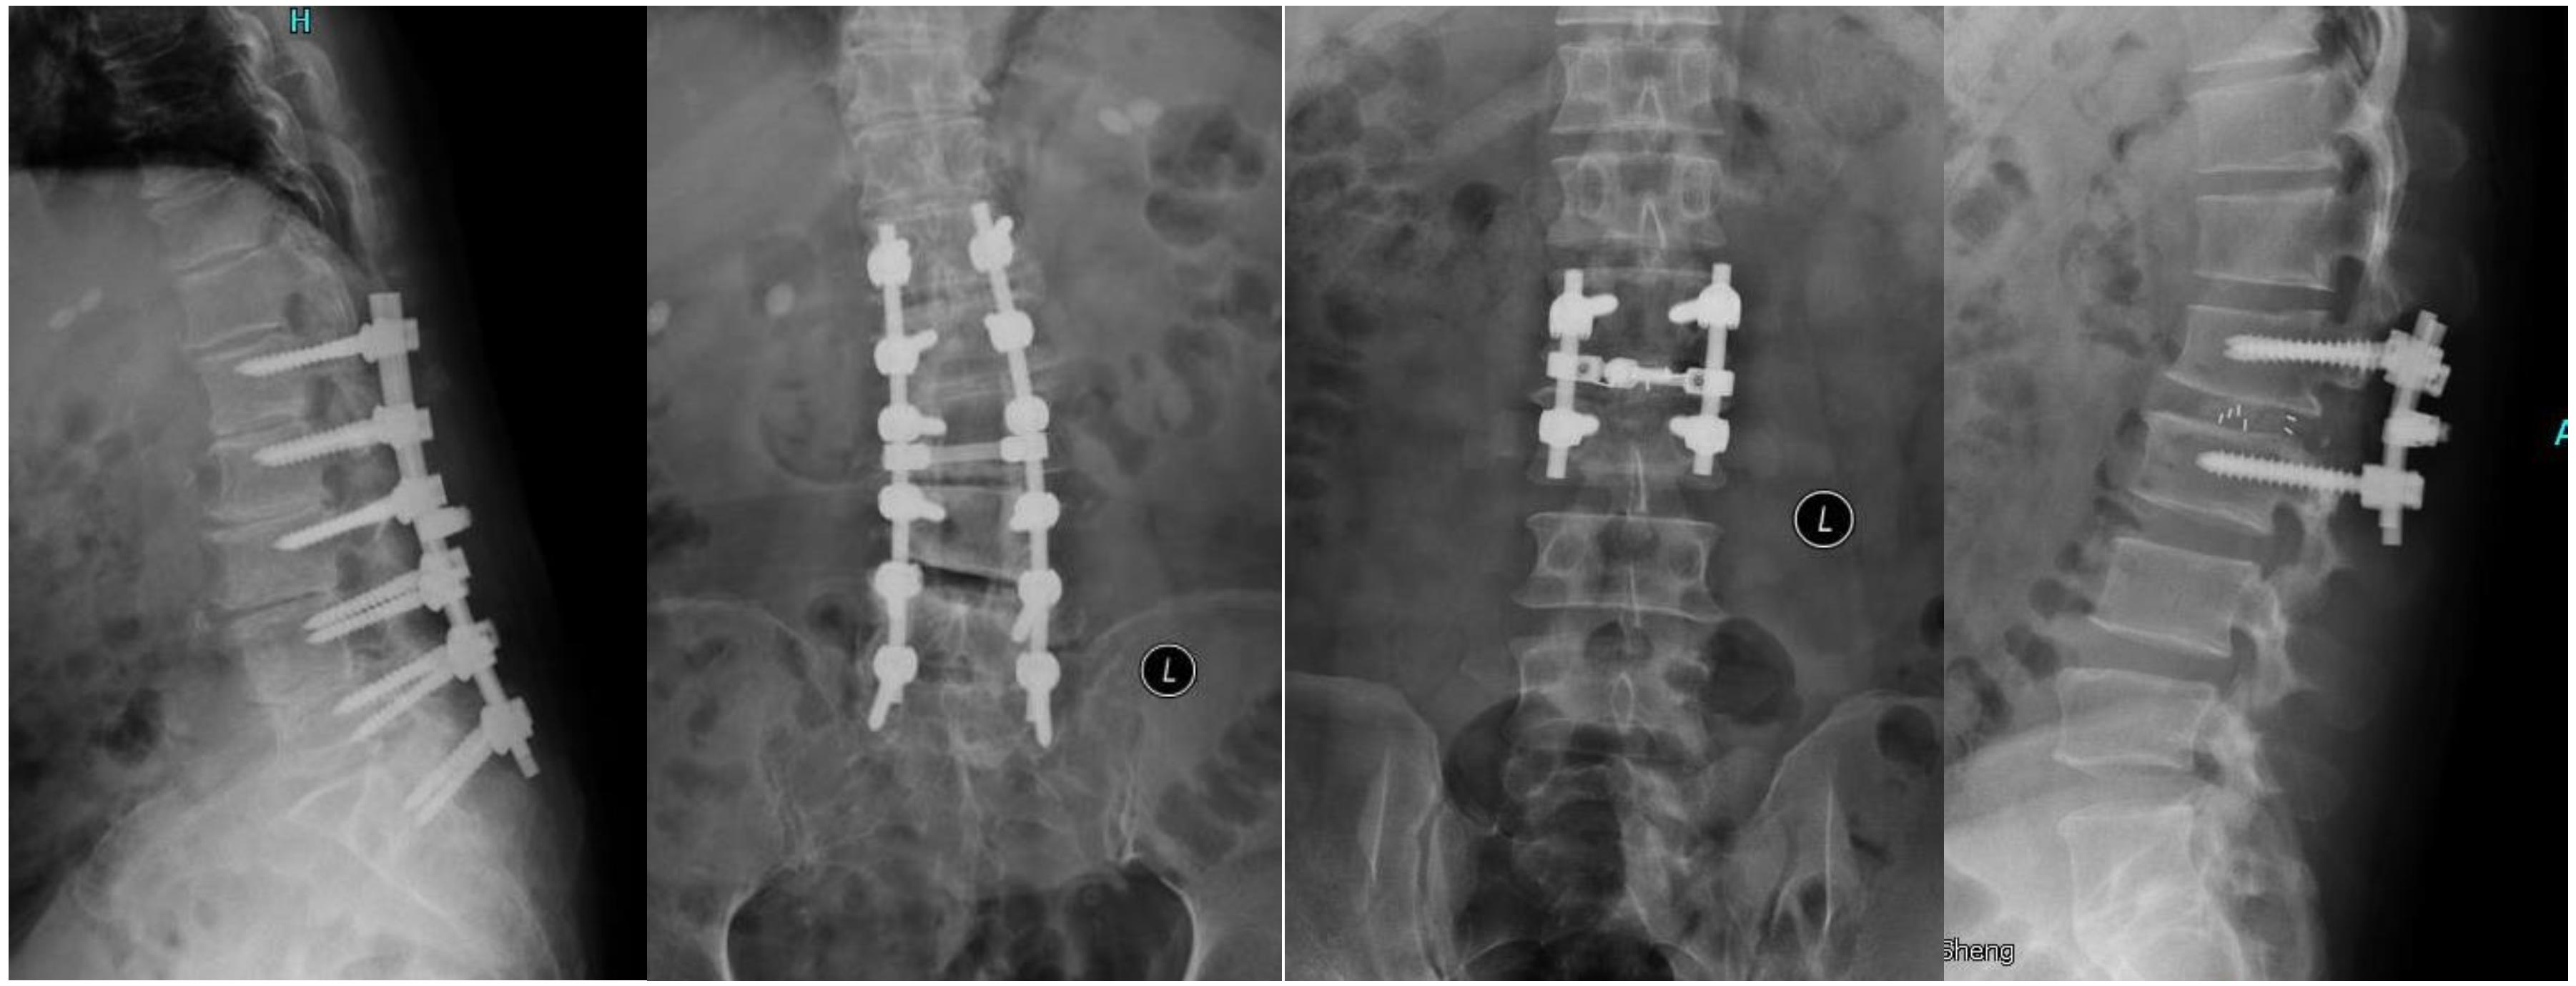

后路腰椎融合术(PLIF)